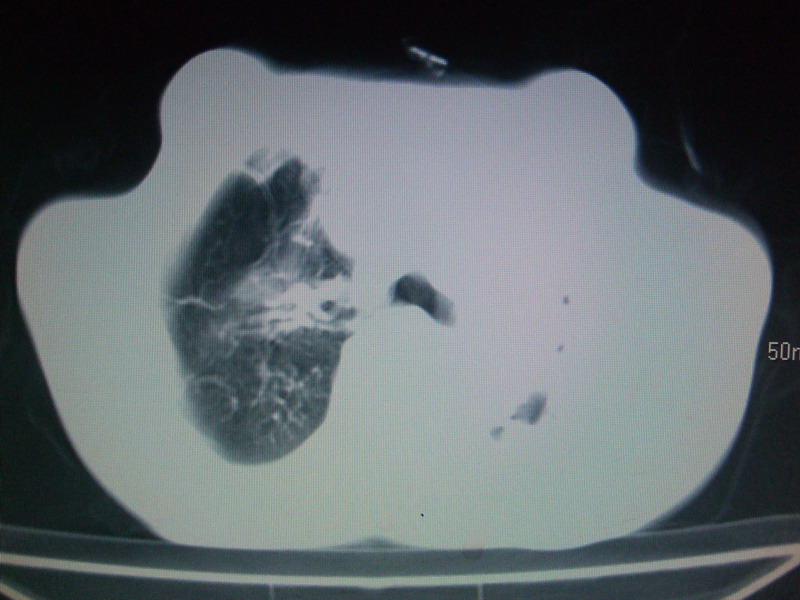

男  70岁,发烧咳嗽4天。盗汗,消瘦。无痰中带血丝,以前有肺tb病史,ct见,双肺tb,左侧胸廓塌陷,左胸膜肥厚粘连。纵隔移位,右侧胸腔积液,大家说说那个心影前左肺舌叶除了肺大炮还有炎症还是干酪性肺炎?有占位吗?我看纵隔淋巴结也大。

是胃,纵膈未见明显肿大淋巴结。

1)两肺继发性肺结核并左肺上叶肺不张,支气管扩张。2)双侧胸膜炎(胸膜增厚+少量胸腔积液)。

双肺继发性肺结核伴部分左肺毁损。